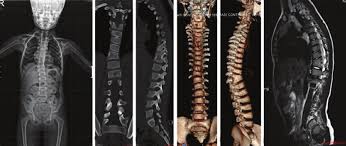

Konjenital skolyozun genetik faktörleri, tanı ve cerrahi planlama stratejileri.